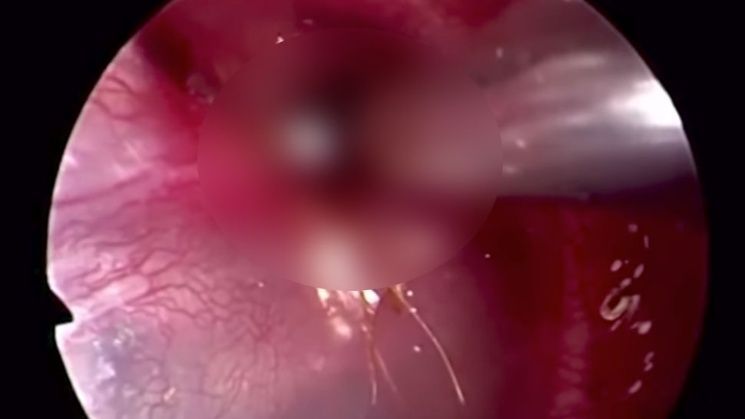

Un médico en Singapur, logro grabar el momento en donde remueve un insecto adherido en el interior del oído de un paciente.

El insecto de ocho patas es un parásito poco común, el cual es muy fuerte y se ve reflejado en el video. Tanto es así, que provocó el sangrado del paciente hasta que pudo removerlo.